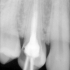

Leczenie endodontyczne, stosowane w przypadku próchnicy powikłanej zapaleniem, martwicą czy zgorzelą miazgi zębowej polega na usunięciu z komory i kanałów korzeniowych zęba zainfekowanej lub martwej miazgi, mechanicznym poszerzeniu i odkażeniu kanałów oraz szczelnym ich wypełnieniu specjalnymi materiałami.